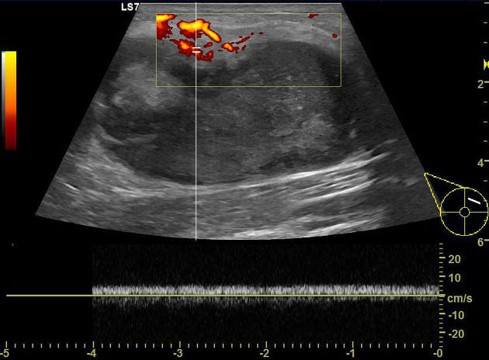

The ultrasound features of an abscess include:

-

A well-circumscribed, irregular hypoechoic to heterogenous, typically multiloculated, lesion

No internval vascularity

Posterior acoustic enhancement from fluid

Echogenic, vascular rim (or thickened wall).10,11

Image 2

Image 3

Images 2 and 3: Trop et al 2011 (12)